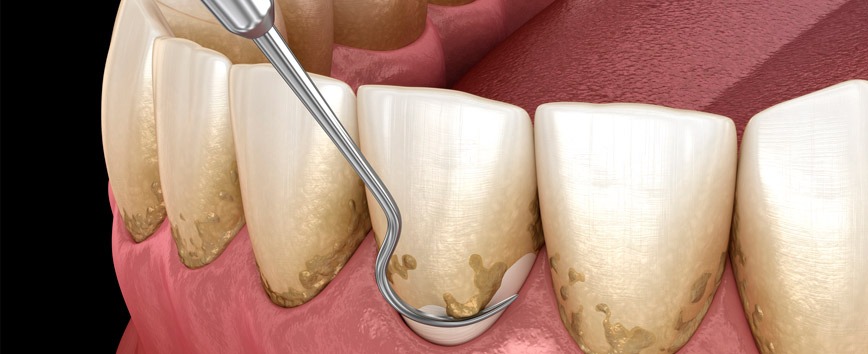

Higiéne Oral

Prevenção de doenças orais através de remoção da placa bacteriana e de resíduos alimentares.